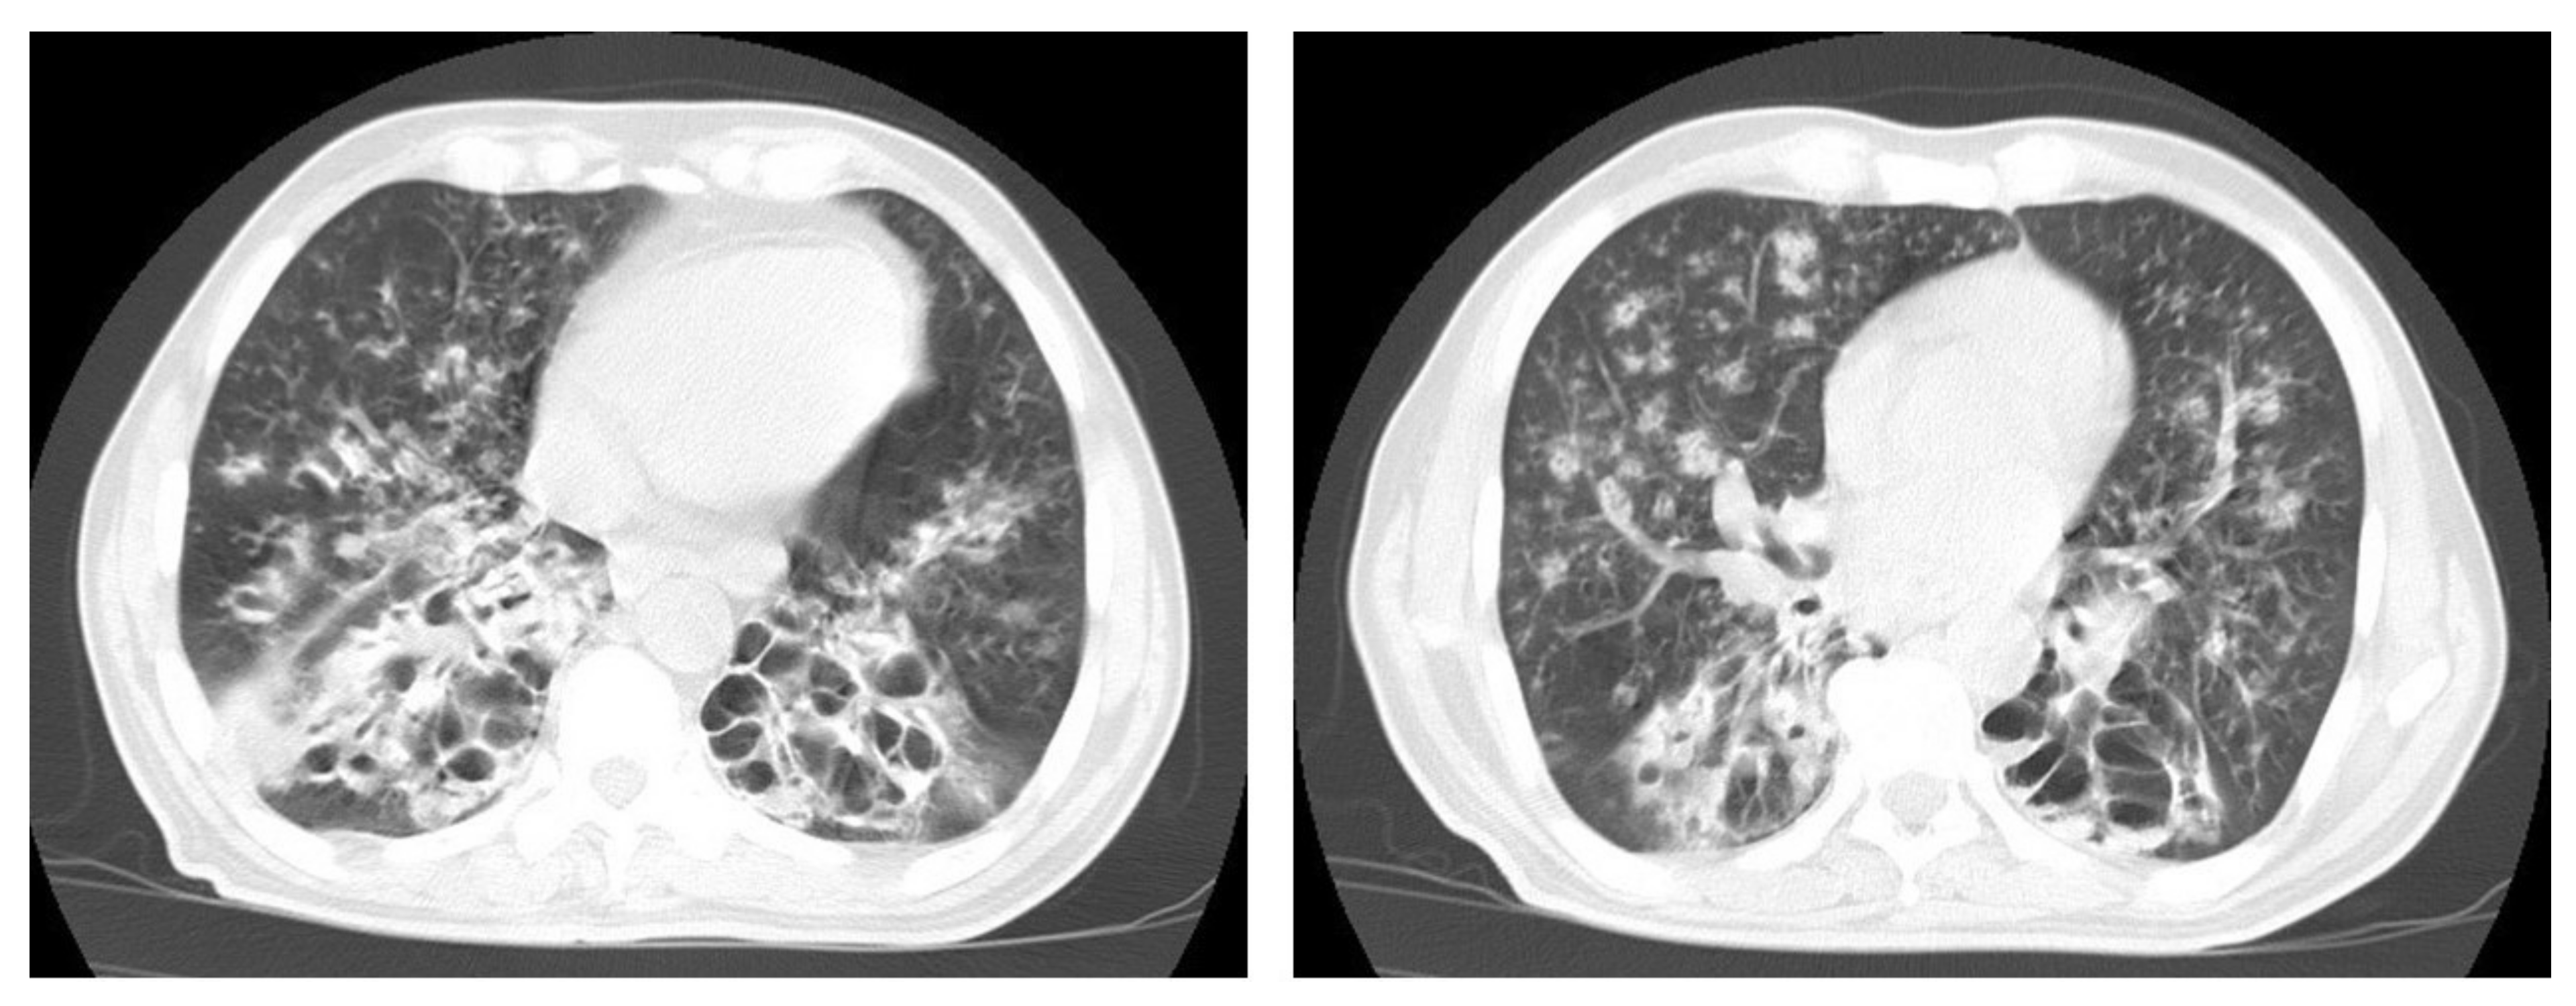

Figure 9. Old reactive TB with superimposed infection in a 75-year-old female with chronic cough and no history of previous medication. Selected axial images of lung CT show prominent fibrotic changes with scarring traction bronchiectasis and decreased volume in the apical and posterior segment of the upper lobes and architectural distortion of the lung parenchyma caused by cystic bronchiectasis predominantly involve bilateral lower lobes, ligula, and right middle lobe. Patchy consolidative areas and ground glass opacities are signs of active infection.

Figure 10. Reactivation of TB in an adult man with chronic cough. Selected axial images of lung CT show cystic bronchiectasis, due to old infection, with peribronchial thickening and air fluid level involving both lower lobes. Scattered tree in bud pattern and infected cystic bronchiectasis indicate active TB.

Even after full treatment of pulmonary TB, complications and residual changes may affect quality of life; these complications can be misinterpreted as other active diseases, causing diagnostic pitfalls. TB complications in the lung parenchyma include tuberculoma, thin-walled cavities, cicatrisation collapse (Figure 9), and lung cancer, although this is rare. Complications in the airway include bronchiectasis (Figure 10) and tracheobronchial stenosis. Extrapulmonary complications include pleural thickening and calcification, fibrothorax, bronchopleural fistula, and pneumothorax (Figure 11). Vascular complications include Rasmussen aneurysm, calcified mediastinal lymph nodes, fibrosing mediastinitis, and constrictive pericarditis [23].